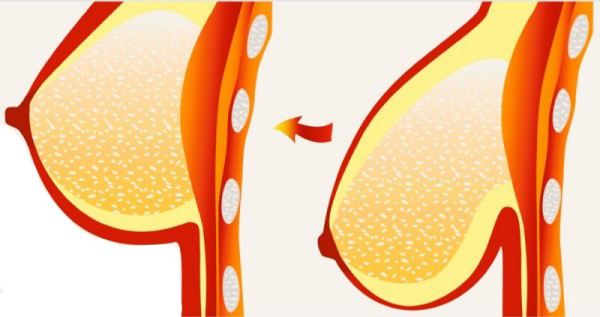

نکاتی چند در مورد تکامل و آناتومی پستان

در این مطلب دکتر مهدی جعفری فوق تخصص جراحی پلاستیک و زیبایی و بهترین جراح زیبایی به ترجمه تخصصی مقاله ای معتبر در خصوص آناتومی پستان در زمینه های مربوط به جراحی سینه ، پروتز سینه و لیفت سینه از منابع معتبر پرداخته اند.

بازسازی سینه در جراحی زیبایی سینه با پروتز

زمانی که عمل بازسازی سینه یا جراحی سینه صورت می گیرد هدف اصلاح نمودن تغییرات بدن و یا برگرداندن سلامتی به شخص می باشد. امروزه بسیاری از بانوان جهت درمان سرطان سینه به انجام جراحی سینه می پردازند ، در جراحی سینه بخش زیادی از بافت پستان حفظ می شود ، در جراحی سینه فقط بخش کوچکی از سینه را بر می دارند.

کوچک کردن سینه ماموپلاستی

ماموپلاستی یکی از انواع جراحی پلاستیک است که هدف آن تغییر سایز پستان (کوچک کردن سینه) بوده تا با تغییر فرم و کاهش سایز آنها به زیبایی اندام کمک کند بنابراین میتوان ماموپلاستی را یکی از انواع جراحی زیبایی به شمار آورد،گرچه در مواردي كه سينه خيلي بزرگ است و باعث مشكلات ساييدگي مهره هاي گردني مي شود،مي تواند درماني نيز محسوب شود.

رفع افتادگی سینه با لیفت سینه

یکی از شایع ترین مسائل زنان به خصوص در سنین بالا رفع افتادگی سینه است که این مورد می تواند با عمل زیبایی ماستوپکسی یا لیفت سینه بر طرف شود، در این مطلب از وب سایت...

دستورالعمل های جراحی پروتز سینه

در این مطلب دکتر مهدی جعفری فوق تخصص جراحی پلاستیک و زیبایی و بهترین متخصص زیبایی و جراح زیبایی به توضیح دستورالعمل های ضروری قبل و بعد از انجام جراحی پروتز سینه و بزرگ کردن سینه پرداخته اند.